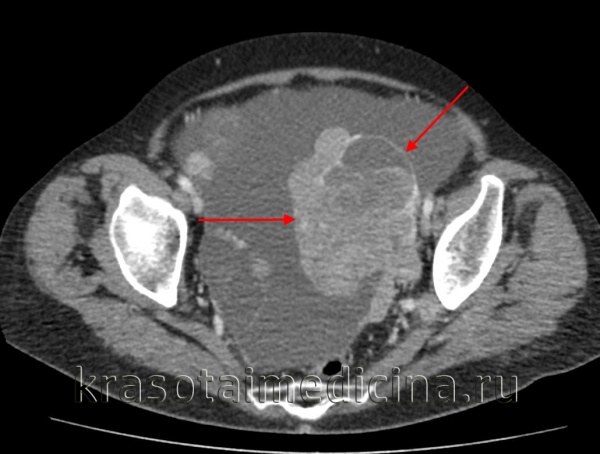

- Методы визуализации. С помощью трансвагинальной эхографии (УЗИ), МРТ и КТ малого таза выявляется объемное образование неправильной формы без четкой капсулы с бугристыми контурами и неодинаковой внутренней структурой; оцениваются его размеры и степень распространенности.